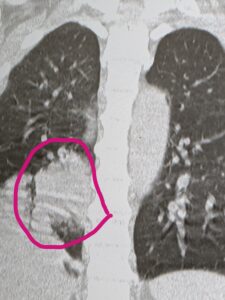

長引く咳は、CTをかならずとりましょう

50代男性です。

咳がなおらないということで

受診されました。

CTで、右の肺に腫瘍を認め、総合病院に紹介しました。

2週間以上の咳は、必ず咳をとりましょう。